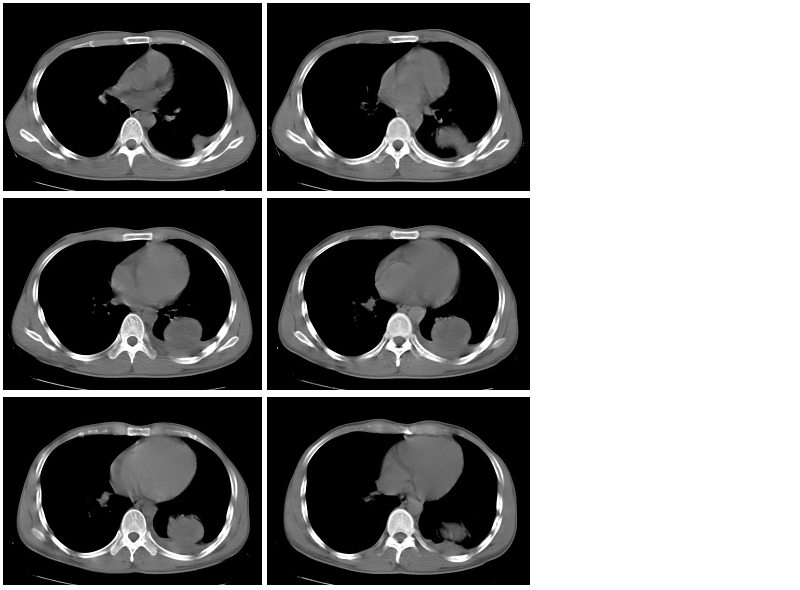

男性,34岁,咳嗽,胸痛一个月,左下肺呼吸音清。分别是肺窗(1-2),纵隔窗(3),增强动脉期(4),平衡期(5),平扫ct值为40-50hu,增强后厚壁达到80-100hu, [/color]

类圆形肿块,强化显著,内液化区无强化,考虑左下肺脓肿,左侧少量胸腔积液。

左下肺可见类圆形高密度影,可见双环征,增强后,壁强化明显,内低密度影未见强化,同侧胸腔积液,左下肺脓肿。治疗后复查。